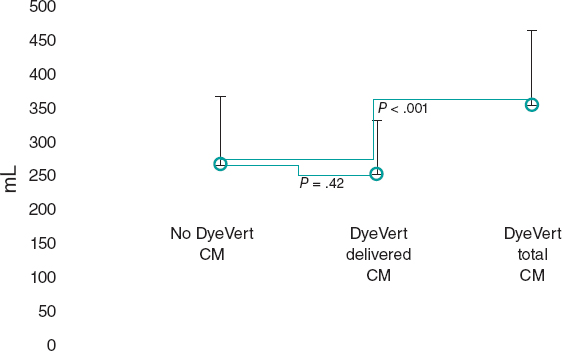

Debulking techniques like rotational atherectomy, orbital atherectomy or excimer laser coronary atherectomy are commonly used to treat calcified coronary lesions. Back in 2018, in Spain up to 1517 patients were treated with rotational atherectomy and 88 with excimer laser coronary atherectomy.7 Recently, the ICL has emerged as an attractive option for the management of patients with severely calcified coronary lesions. Nevertheless, the experience reported on this new technique is still limited. The recently published single-arm Disrupt CAD II clinical trial confirmed the safety and performance of ICL to treat calcified coronary lesions.5 However, the clinical characteristics of the patients enrolled in this trial show a relatively low-risk population. Complex calcified coronary lesions are a common thing and they amount to 25% to 30% of all PCIs performed.3 Among our population, 2.7% of patients were considered eligible to receive ICL therapy, indicative of a highly demanding indication criterion. Compared to the Disrupt CAD II clinical trial5 our patients were younger but had a worse clinical scenario with a higher prevalence of diabetes (68% vs 32%) and renal failure (22% vs 9%), and up to 76% had suffered an acute coronary syndrome (none in the Disrupt CAD II trial). Another recent report described the initial experience with ICL in a cohort of 26 patients with calcified coronary lesions with findings for the clinical characteristics and results similar to the Disrupt CAD II.8